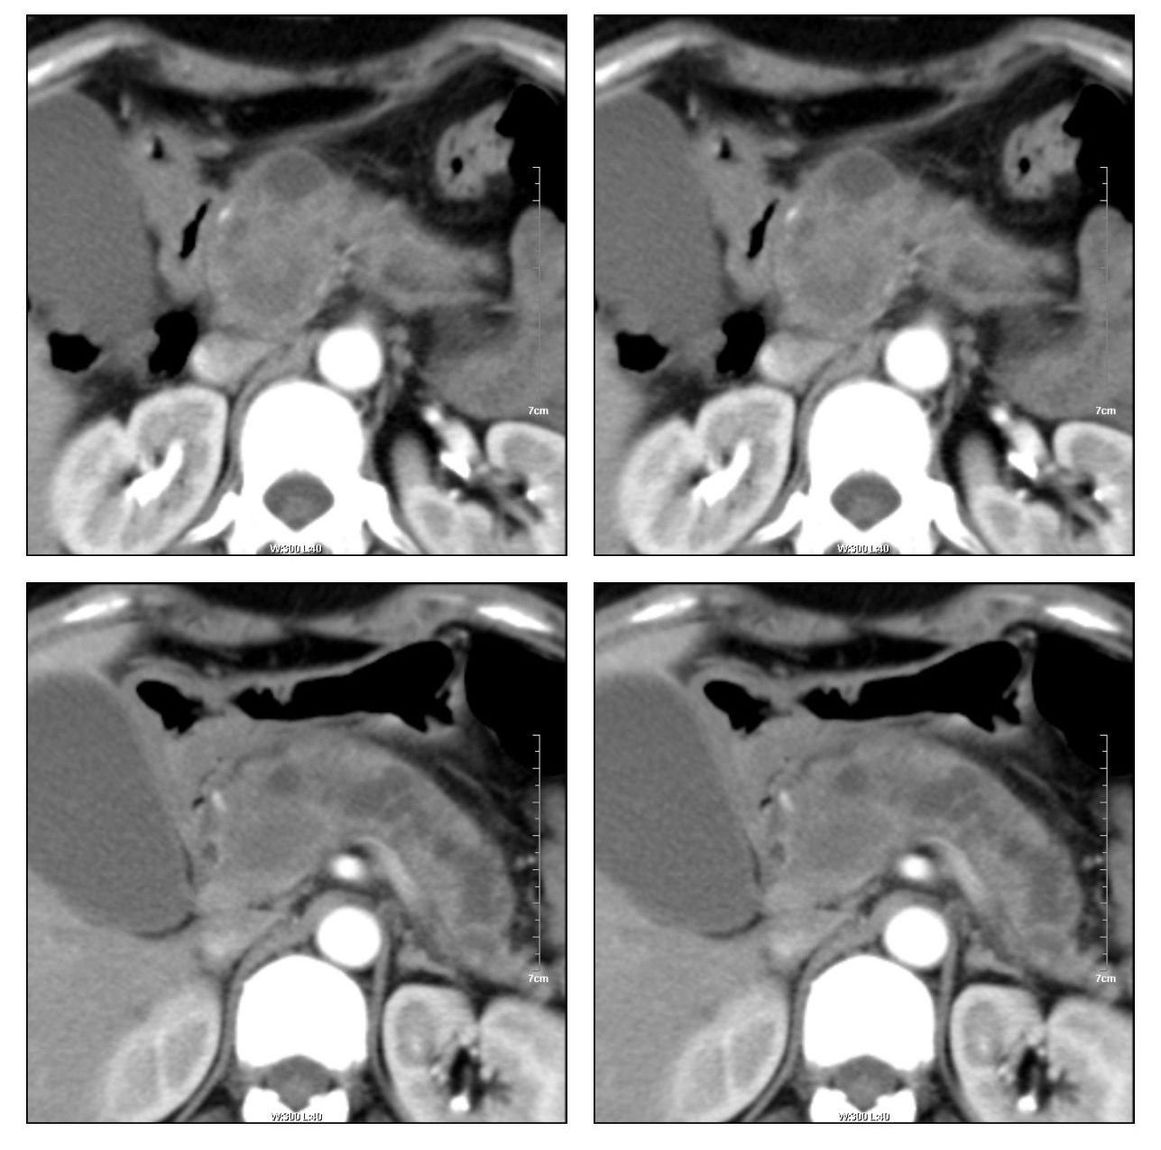

标题: CT13800:女性,52岁。腹痛、腹胀、消瘦及乏力5个月。 [打印本页]

标题: CT13800:女性,52岁。腹痛、腹胀、消瘦及乏力5个月。

慢性胰腺炎、胰腺假囊肿形成,胆总管梗阻,胆囊扩张

胰腺癌可能大

考虑胰头癌

慢性胰腺炎、胰腺假囊肿形成,胆总管梗阻,胆囊扩张,不除外胰腺占位

考虑胰腺囊腺癌。

考虑胰头癌可能。

考虑胰头癌可能性大。

各期时间抓的不太好,门静脉始终显示不佳(门脉瘤栓形成?)。